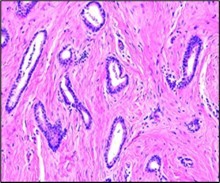

Figure 1.Tubular carcinoma delineating tubules layered by cuboidal to columnar epithelial cells impregnated with miniature to intermediate nuclei, apical snouts and surrounding desmoplastic stroma 7.

Around > 90% of tumefaction is comprised of miniature, ovoid or angulated tubules demonstrating open lumens. Neoplastic tubules are coated by singular layer of cuboidal to columnar epithelial cells impregnated with uniform, miniature to intermediate, low grade nuclei. Frequently, tumour cells display apical cytoplasmic tufts or snouts. Intraluminal secretion or calcification may be discerned. Neoplastic tubules appear devoid of encompassing myoepithelial cells.

Upon microscopy, invasive tubular carcinoma breast configures as a grade I neoplasm and expounds an infiltrative pattern of tumour evolution. Frequently, invasion of tumour cells into circumscribing adipose tissue and fibrous tissue stroma may ensue or a desmoplastic stromal response may be evoked3, 4.

Mitotic activity is minimal. Neoplasm is devoid of significant cytological atypia, multi-layering or enhanced mitotic activity 3, 4. Neoplastic cells appear immune reactive to oestrogen receptors (ER) and immune non reactive to HER2.

Two dimensional microscopic features and three dimensional modelling studies exhibit a neoplastic structure simulating a ‘necklace’ configured of string of beads wherein neoplastic tubules are visualized as blebs with solid cellular cords appearing as intervening bridges. Generally, continuous or branching tubules are absent. Surrounding stroma is desmoplastic or appears fibro-elastotic 3, 4. Frequently, neoplasm represents as non-obligate precursor of lesions as